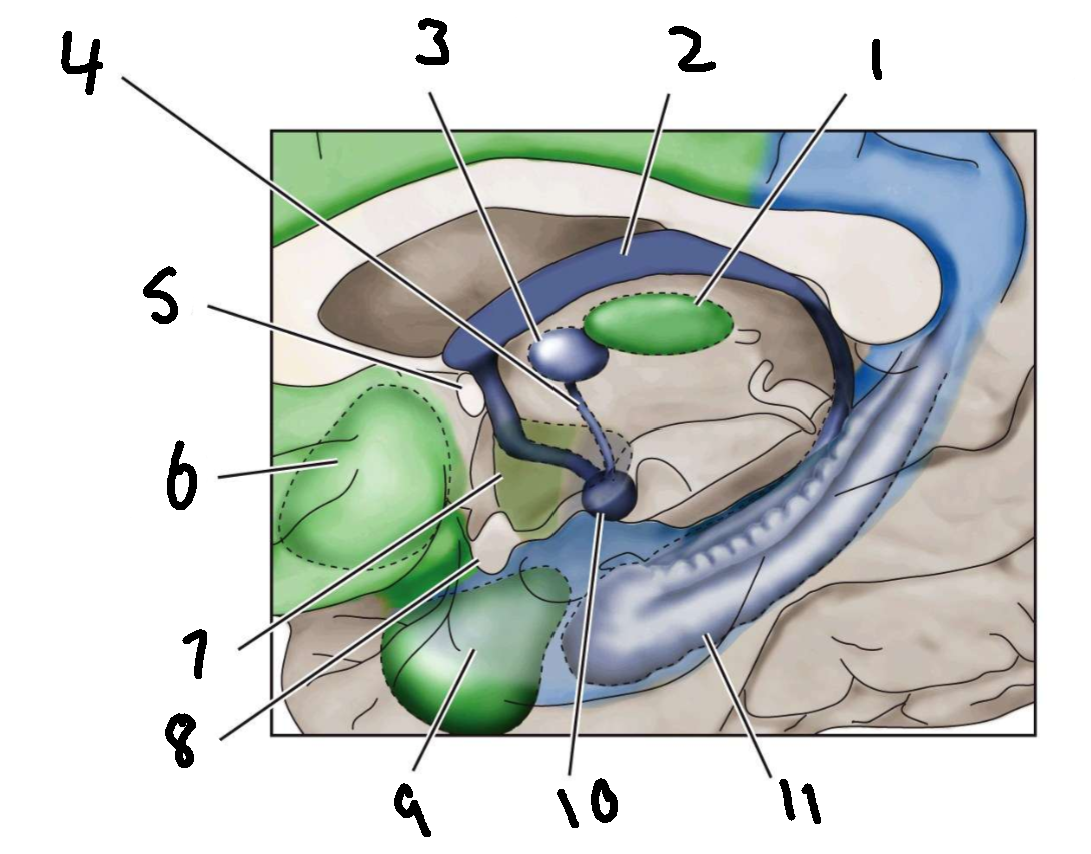

What is 1?

mediodorsal nucleus of the thalamus

What is 2?

fornix

What is 3?

anterior nucleus of the thalamus

What is 4?

mammillothalamic tract

What is 5?

anterior commissure

What is 6?

ventral basal ganglia

What is 7?

hypothalamus

What is 8?

optic chiasm

What is 9?

amygdala

What is 10?

mammillary body

What is 11?

hippocampus